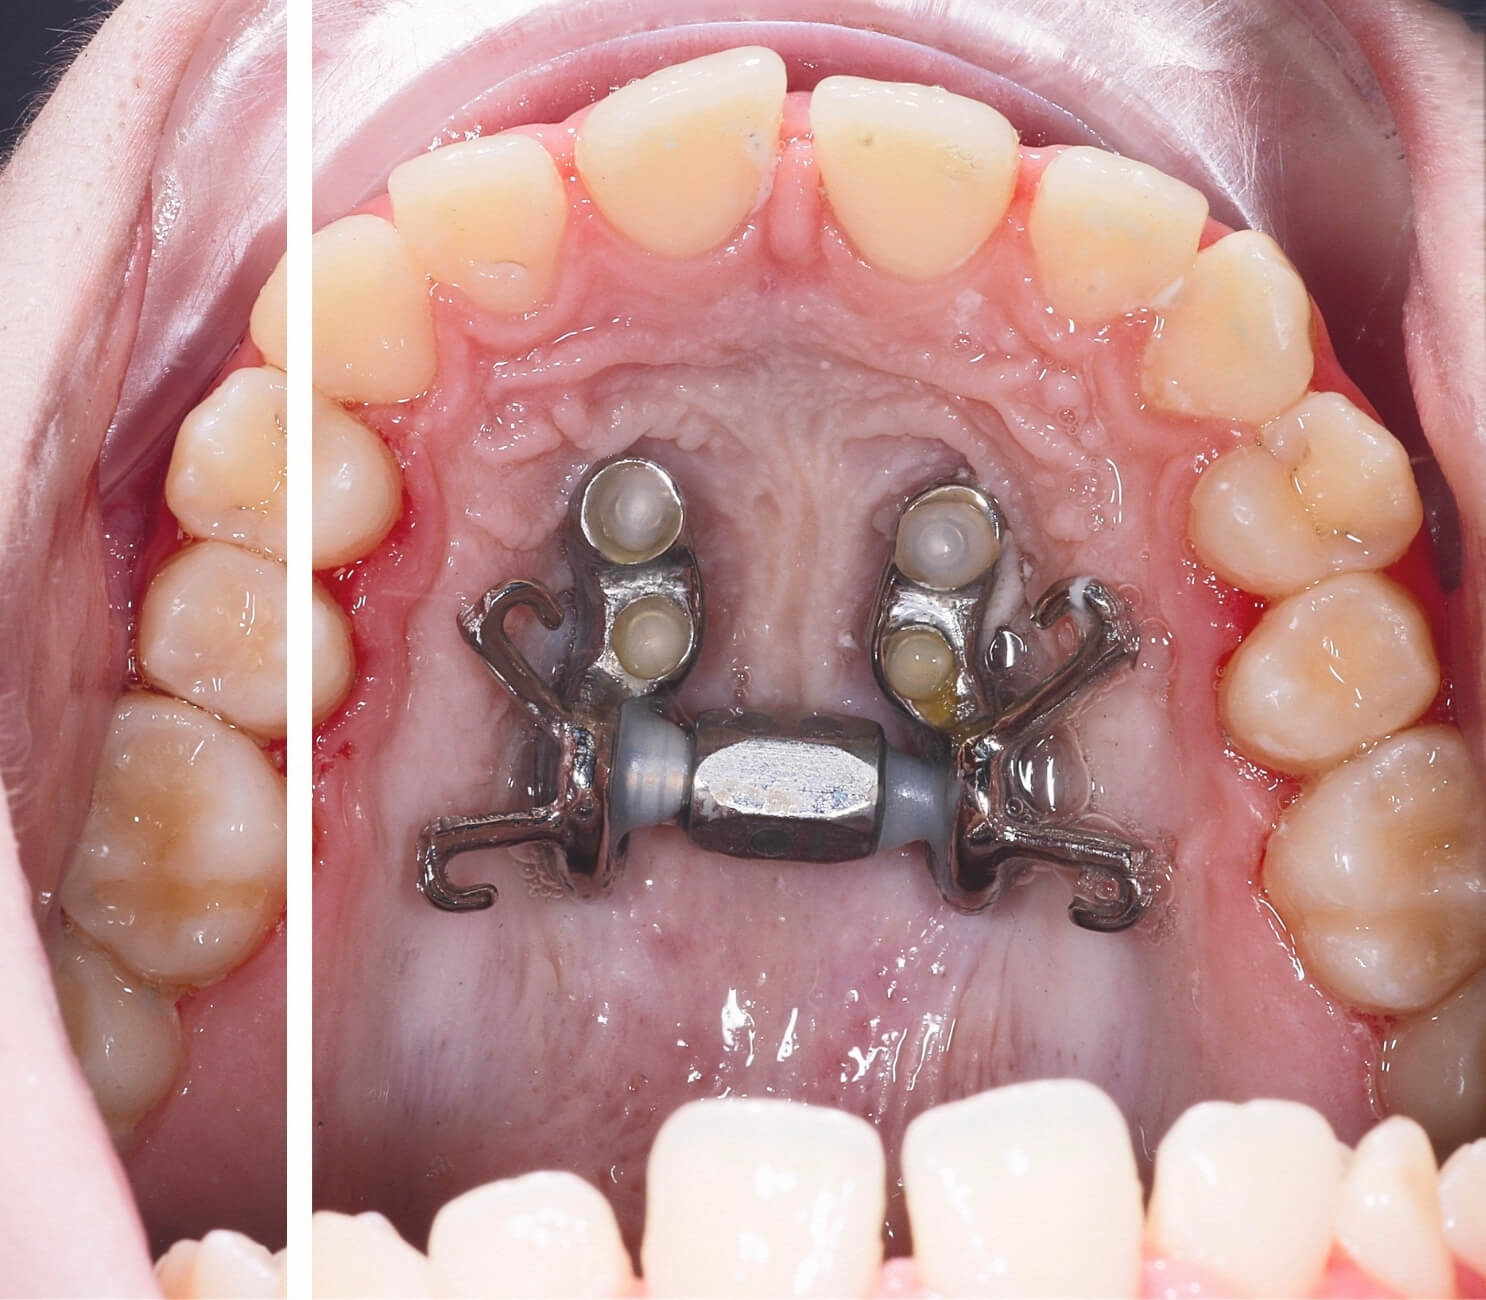

MARPE, “Mini-implant Assisted Rapid Palatal Expansion” ifadesinin kısaltmasıdır. Türkçe karşılığıyla mini vida destekli hızlı üst çene genişletme sistemi olarak tanımlanabilir. Bu yöntemde, üst çeneye özel olarak planlanan aparey mini vidalarla desteklenir ve böylece genişletme kuvvetinin daha kontrollü şekilde iletilmesi amaçlanır. Özellikle büyüme gelişim dönemi sonrasındaki uygun hastalarda üst çene darlığının değerlendirilmesinde önemli bir seçenek olabilir.Böylece hem estetik görünüm hem de günlük yaşam konforu yeniden kazanılabilir.

MARPE, "Mini-implant Assisted Rapid Palatal Expansion" ifadesinin kısaltmasıdır. Türkçe karşılığıyla mini vida destekli hızlı üst çene genişletme sistemi olarak tanımlanır. Bu yöntemde üst damağa lokal anestezi altında 4 adet mini vida yerleştirilir; bu vidaların üzerine özel olarak tasarlanmış bir genişletme apareyi sabitlenir.

Klasik üst çene genişletme apareylerinden farkı, kuvvetin doğrudan kemiğe iletilmesidir. Klasik apareylerde kuvvet azı dişleri üzerinden iletildiği için ileri yaşta dişler devrilir ancak çene gerçekten genişlemez. MARPE'de mini vidalar sayesinde kuvvet doğrudan kemiğe uygulanır; bu sayede üst damak orta hattındaki birleşim noktası (orta palatinal sutur) açılır ve gerçek iskeletsel genişleme sağlanır.

Hasta evde özel bir anahtarla aktivasyon vidasını günlük olarak çevirerek genişletmeyi gerçekleştirir. Aktif aktivasyon dönemi genellikle 2-4 hafta sürer; sonrasında aparey 4-6 ay pekiştirme amacıyla damakta kalır.